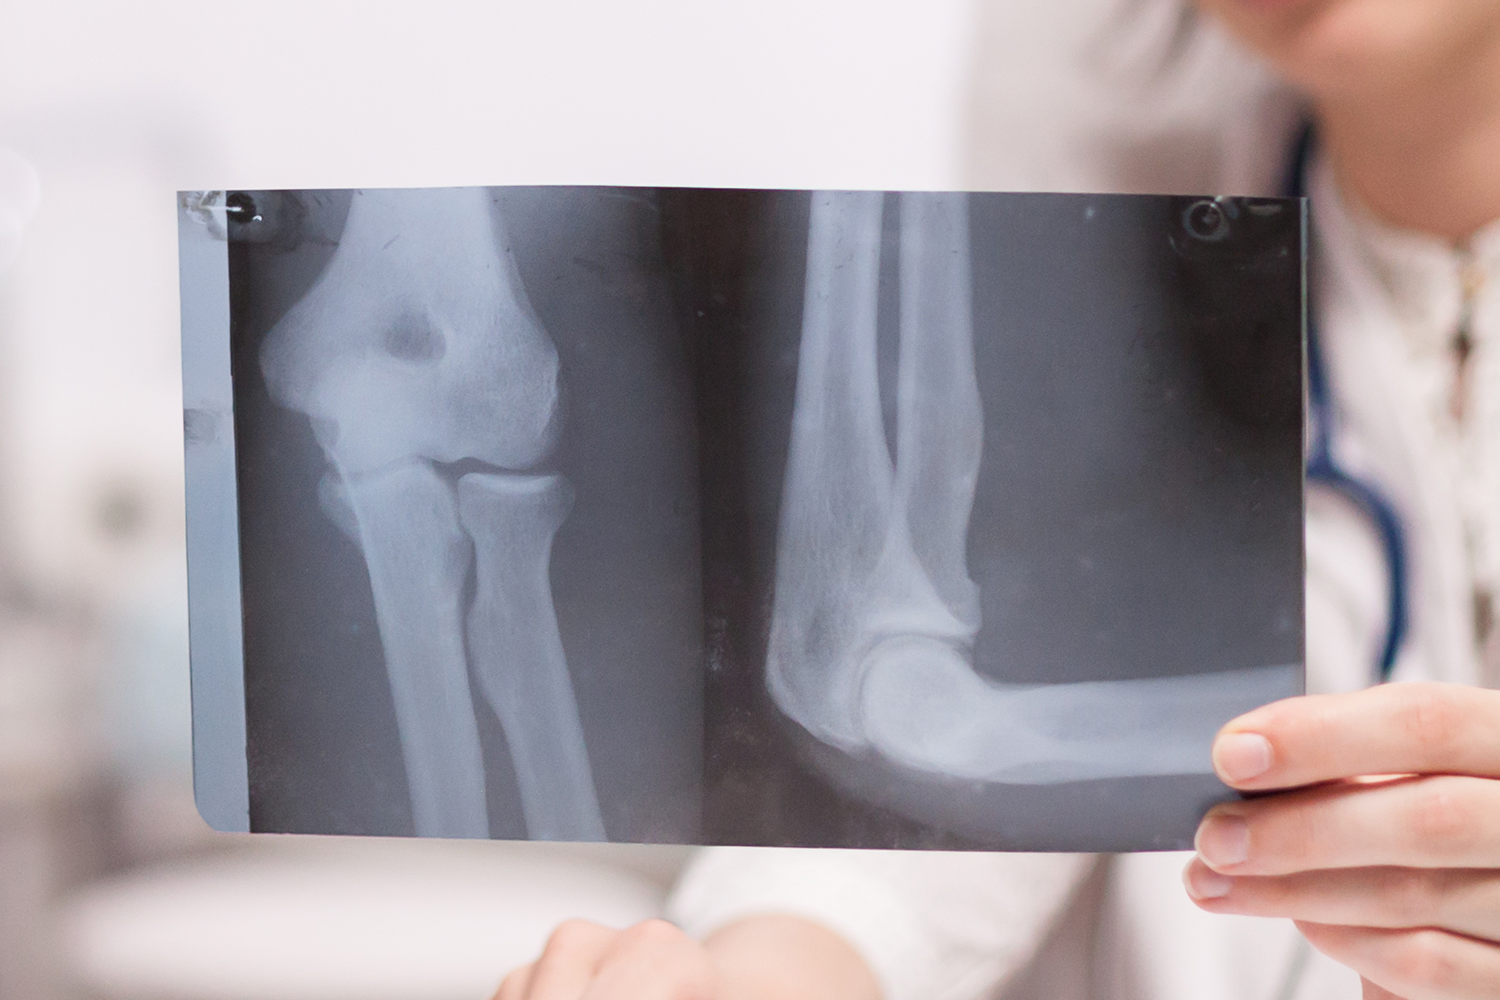

1Twenty80: What are the most effective screening methods for diagnosing osteoporosis in older adults?

Dr. Murugeaswaran Silvaraju:

Screening methods for osteoporosis involve using straightforward tools to assess the likelihood of an individual needing further examination to confirm the condition. One such method is through questionnaires like the Malaysian Osteoporotic Screening Test, which asks about age, weight, height, history of fractures, and family fracture history to calculate the probability of developing osteoporosis over the next decade. An international tool called SCORE (Simple Calculated Osteoporosis Risk Estimation) also helps estimate the risk percentage over time.

Based on these risk factors, individuals may be recommended for a DEXA scan, a bone mineral density test, to confirm osteoporosis.

Additionally, there’s the Fracture Risk Assessment Tool, which provides probabilities of major osteoporotic fractures like those in the spine or wrist, as well as hip fractures. Factors like alcohol use and previous fracture history can influence these risk assessments.

Ultimately, while screening tools like questionnaires can provide initial estimations, the most accurate diagnosis comes from DEXA scans, which categorise bone health as normal, osteopenia (weakened but not yet osteoporotic), or osteoporotic.